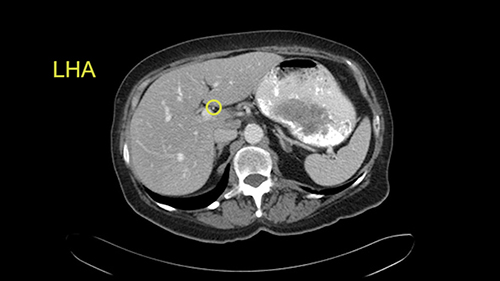

The procedure-specific slowing down moments from a technical point of view for a right hemihepatectomy include a careful evaluation of the inflow structures including the right hepatic artery, the right portal vein, as well to make sure that I have identified and preserved the left hepatic artery and the left portal vein at all times, and minimize any injury or dissection of the common bile duct. Also, I am careful when I mobilize the right liver, not to tear the right triangular ligament and cause bleeding of the liver as I mobilize it off the retroperitoneum and the bare area. In addition, the last procedure-specific slowing down moment is to carefully identify the right hepatic vein and ensure that I encircle it safely without damaging the IVC or the middle and left hepatic vein structures at all times.

In addition, as I plan this operation, I will also look at the size of the small tumors. They’re very small, some are less than one centimetre in size, and carefully evaluate the relationship between the small tumors and the surrounding vascular structures. If I cannot see or feel the tumors at the time of surgery, I will use the blood vessels in order to landmark and plan my operation.

My name is Steven Gallinger, I’m a professor of surgery at the University of Toronto and an HPB surgeon at the University Health Network. I’ve been asked to comment on this case and discuss preoperative planning, potential slowing down moments. It’s an interesting 65-year old woman with right sided colon cancer and synchronous liver metastases: small metastases in the right lobe of the liver and she had the primary tumor resected and then underwent neoadjuvant chemotherapy for her small liver metastases in Segments 4, 5, 6 and 7. The distribution of the metastases is interesting. They are small lesions, but the interesting additional feature is isolated segmental dilatation of the Segment 7 bile duct which suggests an intrabiliary metastasis somewhere near the origin of the main Segment 7 duct. Because I can trace it close to the porta [hepatis], I would assume that it’s pretty close to the bifurcation of the main right sided bile ducts but I can’t actually see the actual tumor. It’s really just presumptive.

She underwent neo-adjuvant chemotherapy and then had a series of additional investigations and the one that I’m focusing on in more finer detail is an MRI with Primovist and I’ve had the benefit of looking at the report. The main issues are in Segments 5,6, and 7. Three small metastases that remain and the radiologist also comments on the lack of biliary dilatation which was present before; implying that the intrabiliary metastasis somewhere at the origin of the Segment 7 duct, has regressed or been adequately well treated with chemotherapy. That’s probably where the difficult decision making comes in the OR. So from an oncologic point of view, I would plan for a right hepatic lobectomy. The rationale would be that this would include the more peripheral Segment 5, 6, 7 metastases that are obvious but also would take care of the presumed Segment 7 intrabiliary metastasis that does not actually visualize on any of the scans but is assumed to be there with evidence of the duct dilatation which then resolved. One could argue whether we should preserve liver and ignore that duct dilatation that was there before but I think my own preference would be to resect the right lobe and that would certainly include any residual disease in that Segment 7 bile duct and moreover, coming back to do a completion right hepatic lobectomy would be difficult particularly around the porta where this metastasis is presumably still there and even if its quite small.

So I would then focus on the hepatic outflow because that’s the way we do the operation is by mobilizing the liver. So the vena cava looks quite normal. The right hepatic vein looks quite normal. There are no large additional outflow veins from the right lobe which would generate slowing down moments. The hepatic artery is unremarkable and is not usually an issue we can define the anatomy quite clearly at surgery.